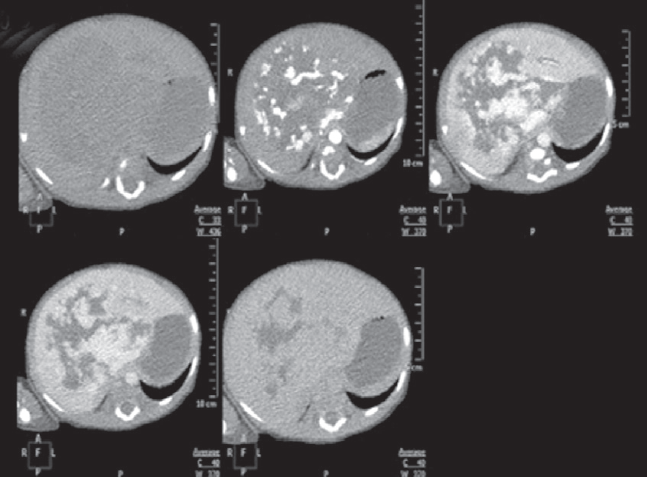

Проведено обследование: УЗИ органов брюшной полости — визуализируется объемное образование с кровотоком, занимающее всю правую долю печени. МСКТ брюшной полости с контрастным усилением — выявлено гигантское сосудистое образование печени срединного расположения (рис. 8).

Рис. 8. Аксиальные компьютерно-томографические снимки во все фазы контрастирования

Fig. 8. Axial CT images in all phases of contrast

При контрольном обследовании в возрасте 3 мес. на УЗИ признаков прогрессирования образования печени не выявлено. МСКТ органов грудной клетки и брюшной полости с в/в контрастированием: в легких без очаговых и инфильтративных изменений, отмечается умеренное уменьшение объема образования, уменьшение диаметра и количества сосудов в центральных отделах образования (рис. 9).

Рис. 9. Компьютерно-томографические снимки брюшной полости в различных плоскостях и фазах контрастирования, контроль в 3 месяца

Fig. 9. CT images in various planes and contrast phases, control at 3 months